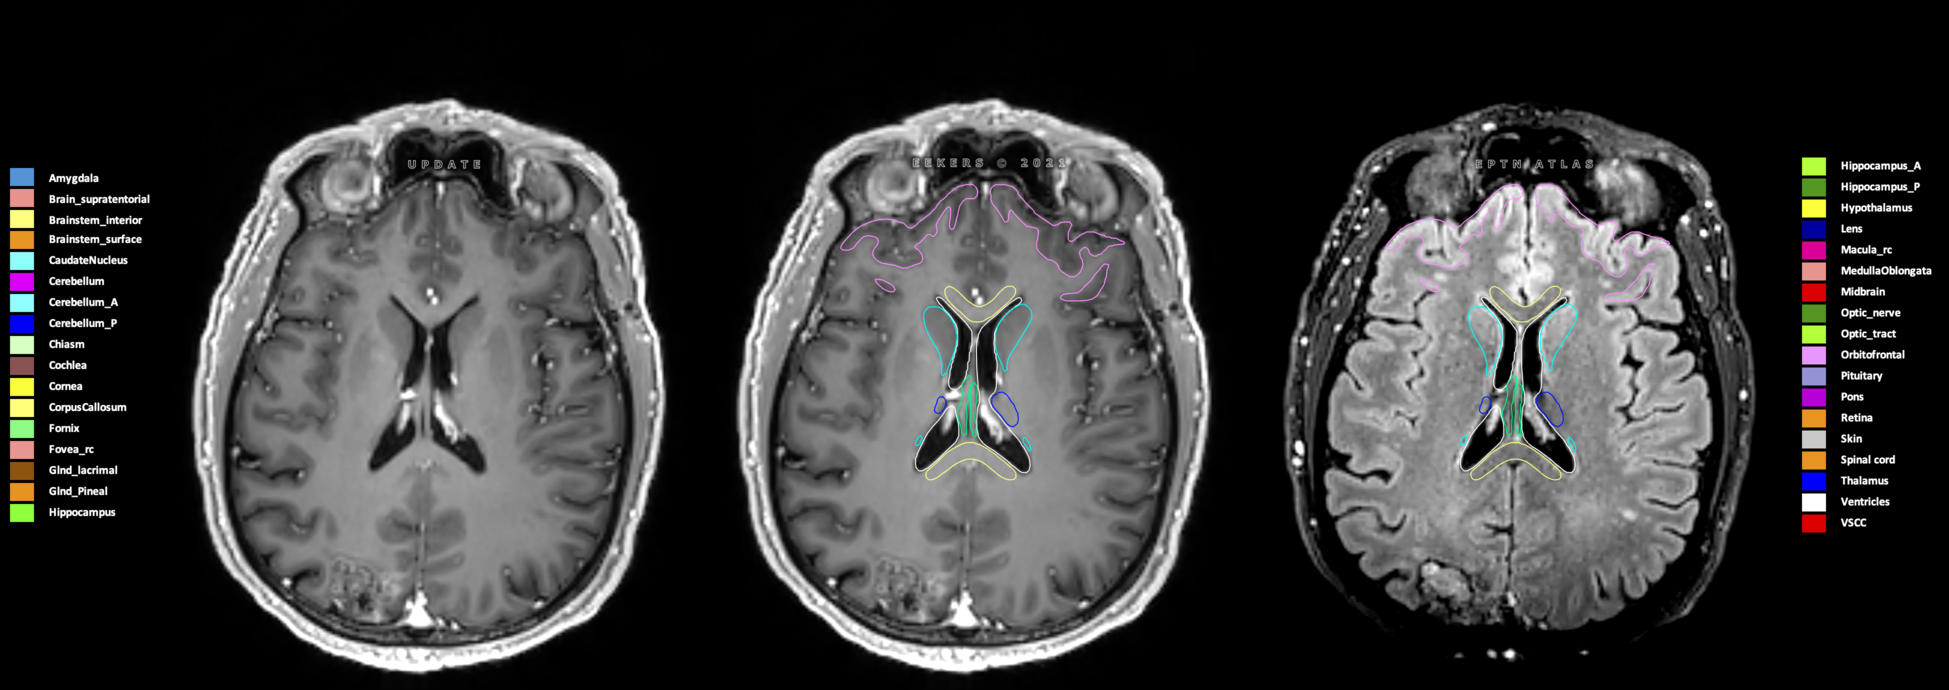

Eekers et al. have published an international neurological atlas for contouring of organs at risk in consensus with the European Particle Therapy Network (EPTN) in 2018 and an update in 2021. The purpose of this consensus atlas is to decrease inter- and intra-observer variability in delineating OARs relevant for neuro-oncology.

Included are all OARs known to be relevant for radiation-induced toxicity in neuro-oncology: brain, brainstem (midbrain, pons, medulla oblongata), chiasm, cerebellum (anterior & posterior), cochlea, cornea, hippocampus (anterior & posterior), hypothalamus, lens, lacrimal gland, optic nerve, pituitary, skin, and vestibular & semicircular canals. To further facilitate research on cognition, vision and radiological changes after irradiation of the brain, potential clinically-relevant OARs are included: amygdala, caudate nucleus, cerebellum (anterior & posterior), corpus callosum, fornix, macula, optic tract, orbitofrontal cortex, periventricular space (PVS), pineal gland, and thalamus.

Three-dimensional delineation of the 25 consensus OARs for neuro-oncology are shown on CT (WW/WL 120/40, 3000/600), 3T MR images, (T1Gd, T2FLAIR 1mm) and 7T MR (MP2RAGE 0.7 mm). All are presented in transversal, sagittal and coronal view.